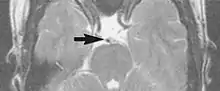

A motion artifact is one of the most common artifacts in MR imaging.[2] Motion can cause either ghost images or diffuse image noise in the phase-encoding direction. The reason for mainly affecting data sampling in the phase-encoding direction is the significant difference in the time of acquisition in the frequency- and phase-encoding directions.[1] Frequency-encoding sampling in all the rows of the matrix (128, 256 or 512) takes place during a single echo (milliseconds). Phase-encoded sampling takes several seconds, or even minutes, owing to the collection of all the k-space lines to enable Fourier analysis. Major physiological movements are of millisecond to seconds duration and thus too slow to affect frequency-encoded sampling, but they have a pronounced effect in the phase-encoding direction. Periodic movements such as cardiac movement and blood vessel or CSF pulsation cause ghost images, while non-periodic movement causes diffuse image noise (Fig. 1). Ghost image intensity increases with amplitude of movement and the signal intensity from the moving tissue. Several methods can be used to reduce motion artifacts, including patient immobilisation, cardiac and respiratory gating, signal suppression of the tissue causing the artifact, choosing the shorter dimension of the matrix as the phase-encoding direction, view-ordering or phase-reordering methods and swapping phase and frequency-encoding directions to move the artifact out of the field of interest.[1]